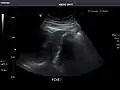

Left kidney